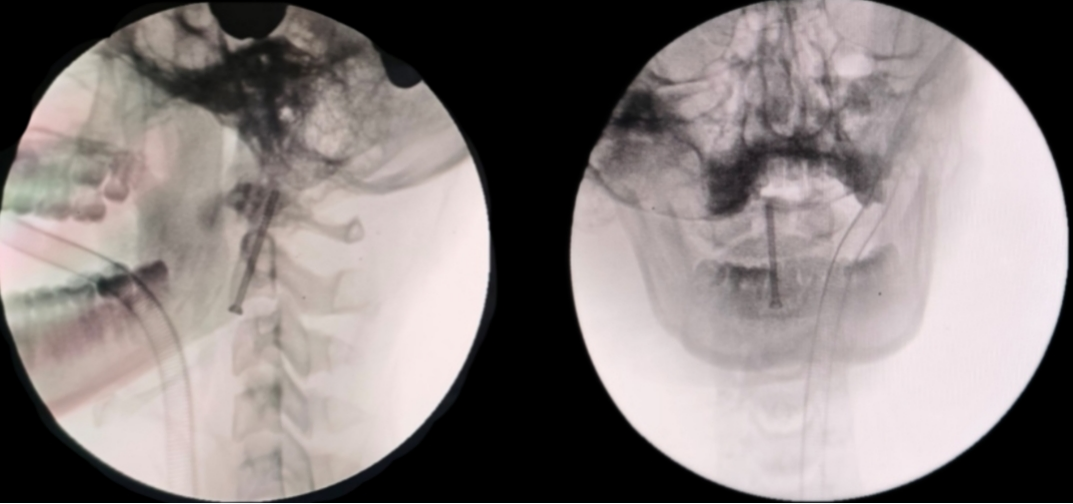

术后第 2 天,小王已经能清醒地和医护人员交流,进行了术后寰枢椎 CT、DR 颈椎开口位片+正侧位片复查,结果显示:枢椎齿状突骨折内固定术后改变,齿状突稍左偏,内固定无松动。